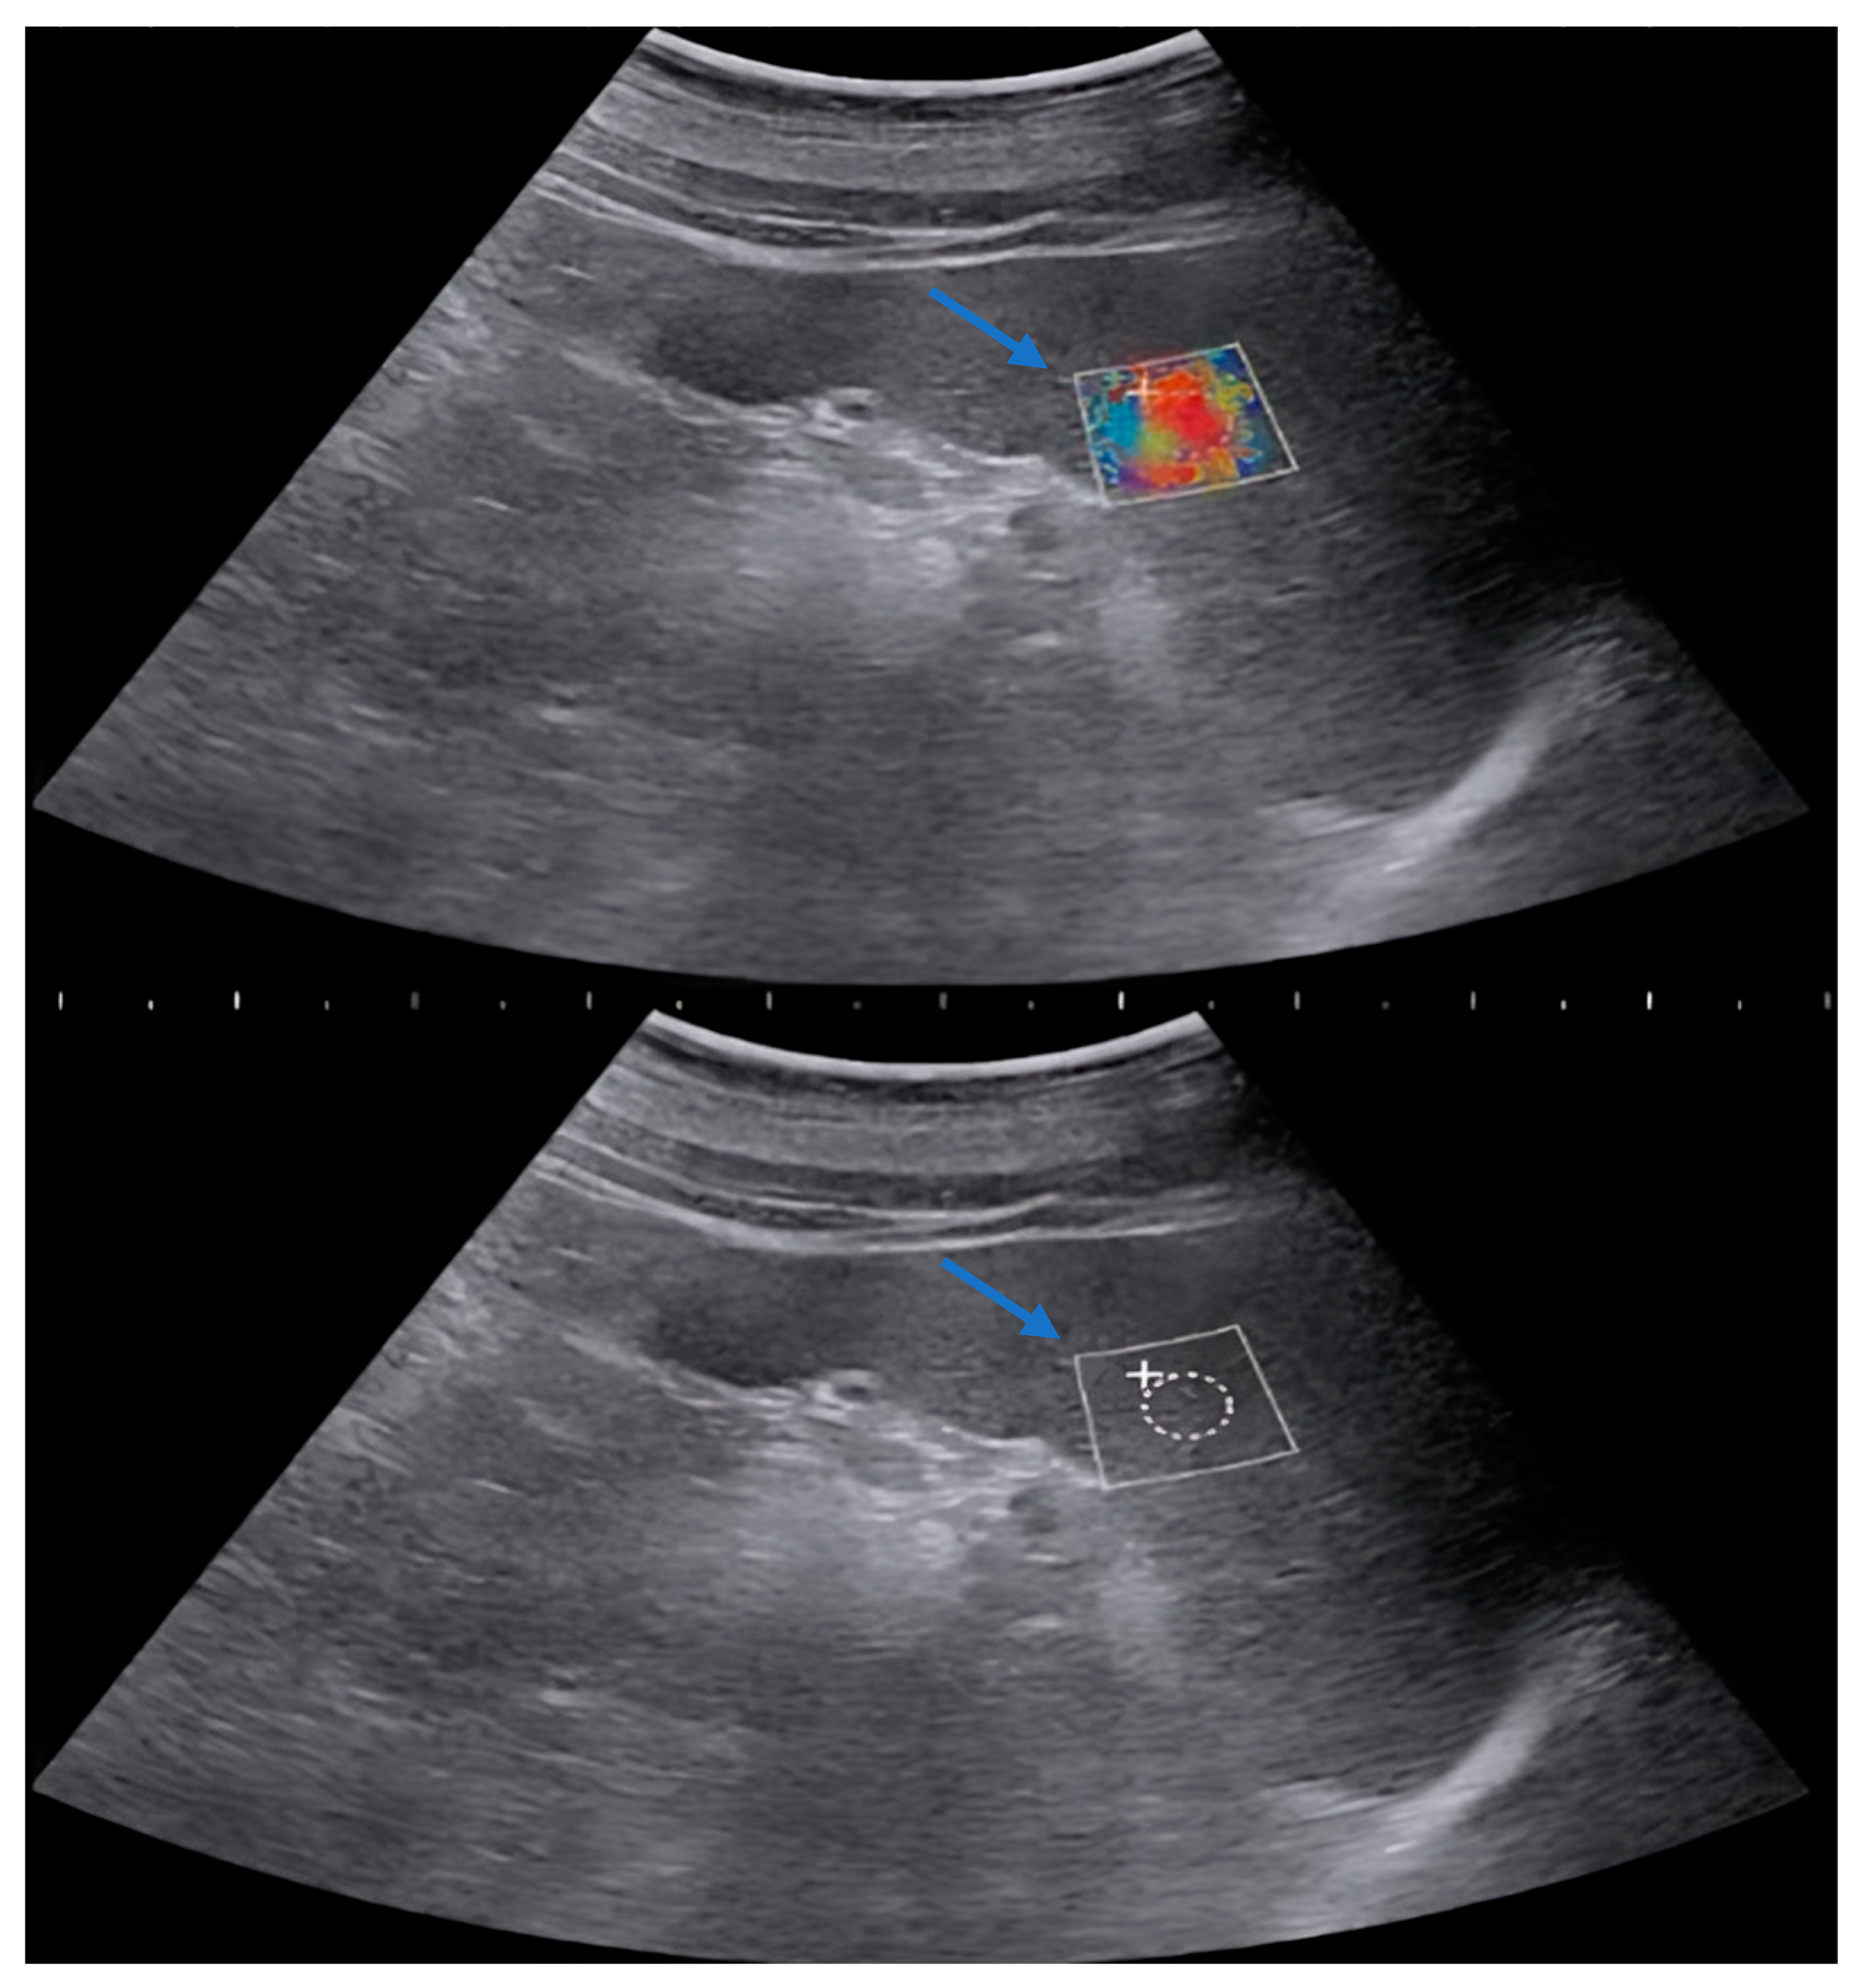

2.2. Methods